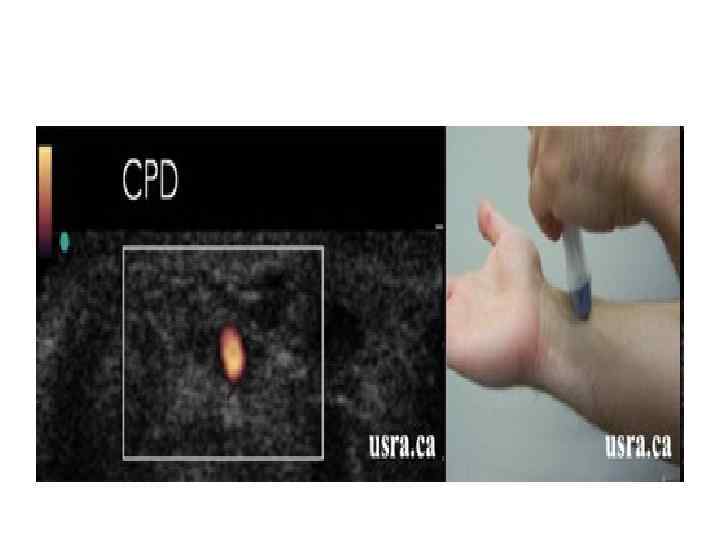

Color Power Doppler (CPD)

Color Power Doppler (CPD)

Энергетический допплер • качественная оценка низкоскоростного кровотока, применяется при исследовании сети мелких сосудов (щитовидная железа, почки, яичник), вен (печень, яички) и др. • Более чувствителен к наличию кровотока, чем цветовой допплер.

Энергетический допплер • качественная оценка низкоскоростного кровотока, применяется при исследовании сети мелких сосудов (щитовидная железа, почки, яичник), вен (печень, яички) и др. • Более чувствителен к наличию кровотока, чем цветовой допплер.

Энергетический допплер На эхограмме обычно отображается в оранжевой палитре, более яркие оттенки свидетельствуют о большей скорости кровотока.

Энергетический допплер На эхограмме обычно отображается в оранжевой палитре, более яркие оттенки свидетельствуют о большей скорости кровотока.

Энергетический допплер • Главный недостаток - остутствие информации о направлении кровотока.

Энергетический допплер • Главный недостаток - остутствие информации о направлении кровотока.

Энергетический допплер Использование энергетического допплера в трехмерном режиме позволяет судить о пространственной структуре кровотока в области сканирования.

Энергетический допплер Использование энергетического допплера в трехмерном режиме позволяет судить о пространственной структуре кровотока в области сканирования.

Энергетический допплер - power doppler • В эхокардиографии энергетический допплер применяется редко, иногда используется в сочетании с контрастными веществами для изучения перфузии миокарда. • Цветовой и энергетический допплер помогают в дифференциации кист и опухолей, поскольку внутреннее содержимое кисты лишено сосудов и, следовательно, никогда не может иметь цветовых локусов.

Энергетический допплер - power doppler • В эхокардиографии энергетический допплер применяется редко, иногда используется в сочетании с контрастными веществами для изучения перфузии миокарда. • Цветовой и энергетический допплер помогают в дифференциации кист и опухолей, поскольку внутреннее содержимое кисты лишено сосудов и, следовательно, никогда не может иметь цветовых локусов.